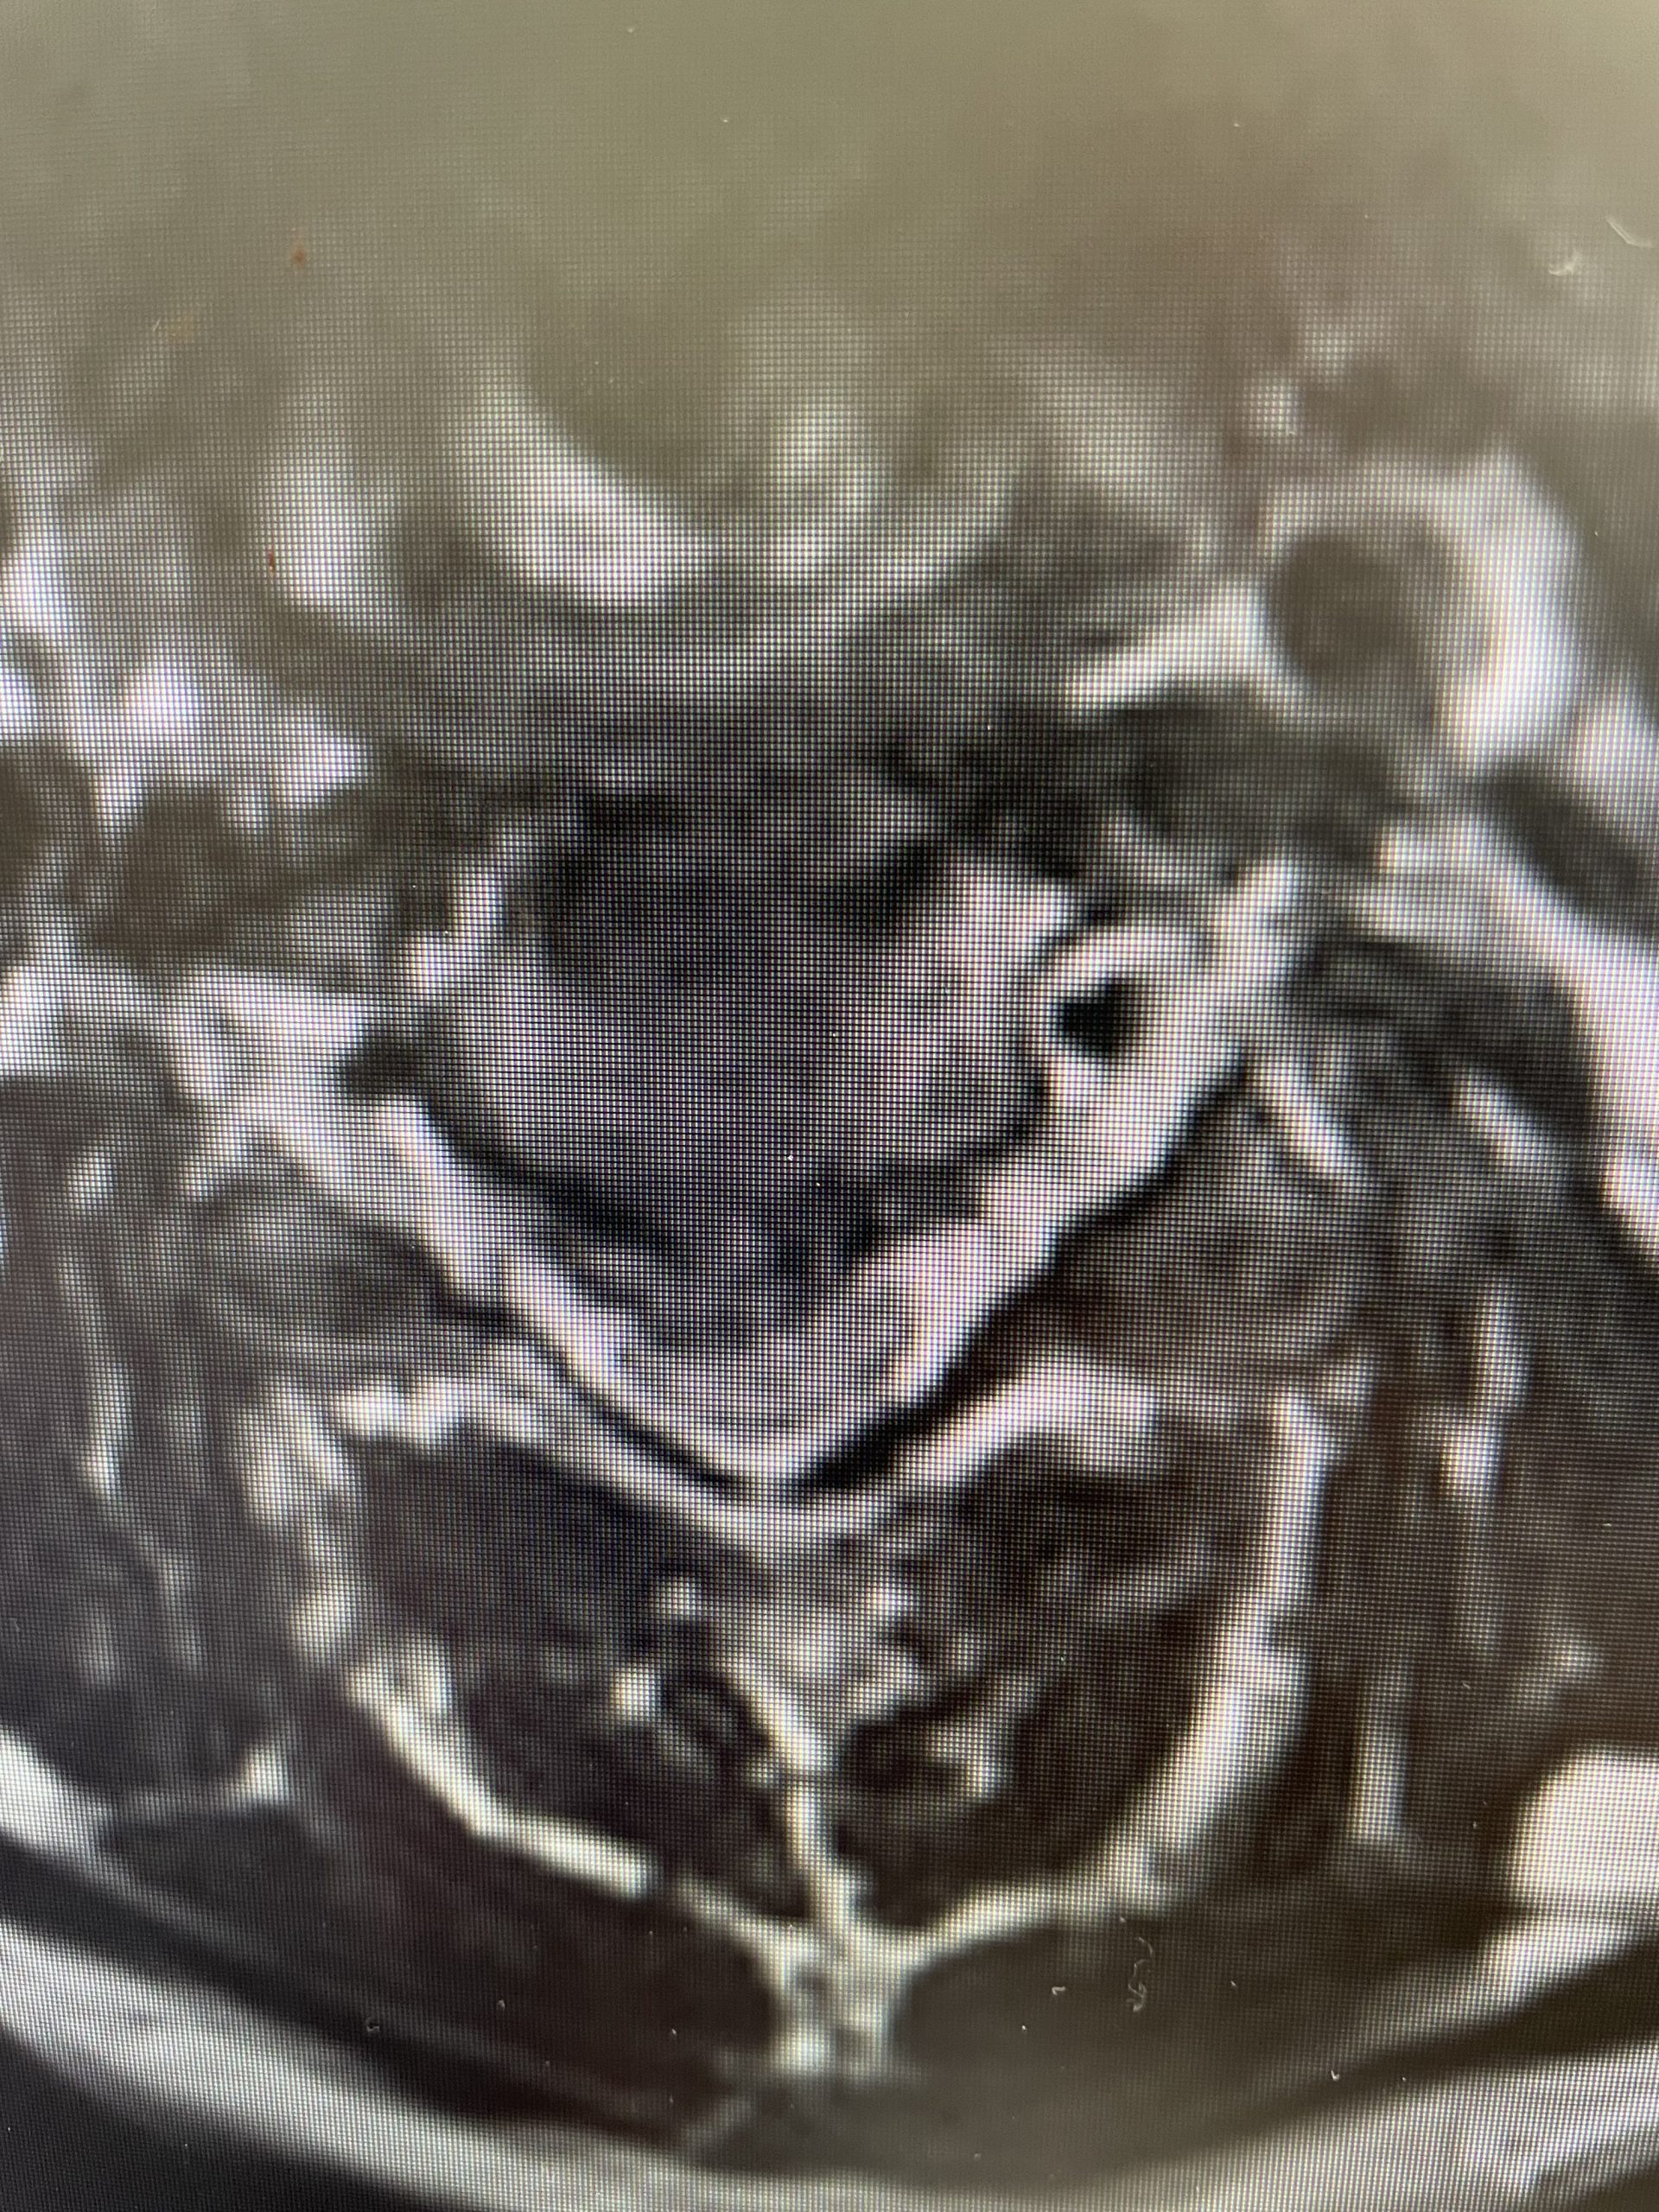

A 69-year-old male presents with chronic low back pain that seems to improve with sitting. The patient had had a prior laminectomy for severe stenosis and in situ fusion five years prior which means that we used bone graft to perform the fusion but no instrumentation. He had done well. Over the last year or so he developed low back pain but no leg pain. The patient had tried all means of conservative management including physical therapy, chiropractic care, acupuncture and epidural injections. Neurologically he was intact. MRI revealed significant stenosis at L2-3 above his prior laminectomy and fusion (Fig 1). We discussed options including surgery. One of the problems we face is a patient with severe stenosis that has severe low back pain with no leg pain. This is particularly challenging when the back pain goes away in flexion or sitting. The quandary is that anecdotally patients with these specific symptoms do tend to improve their back pain after laminectomy, although there are no good studies to support this. Patients with classic neurogenic claudication with pain down their legs when they walk and improved when they sit have a better chance of success. Subjecting a patient to laminectomy for just back pain in the face of having prior surgery puts the patient at risk for not only a potential dural leak because of scarring, but also there may be less of a chance of relieving the back pain than if the patient has leg symptoms. After a discussion, since the patient for the most part is able to manage with conservative treatment modalities is just wait and see over the next three months.